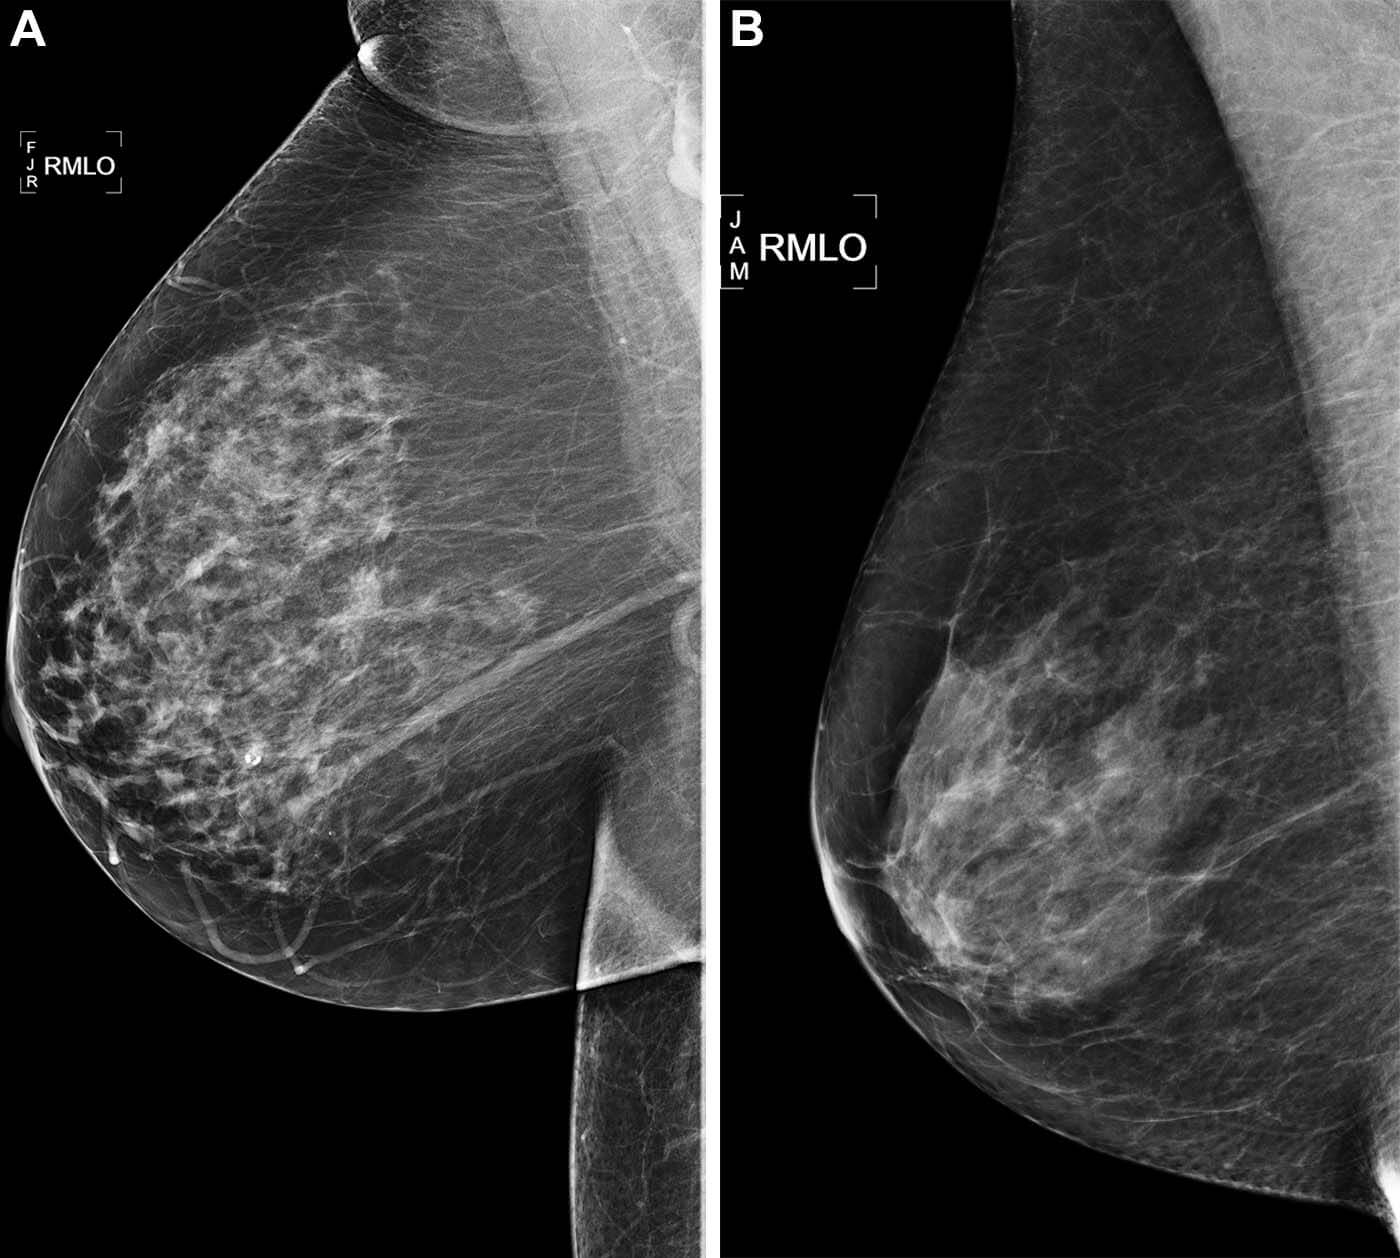

Machine learning algorithms outperform the current methods in predicting the five-year likelihood of the disease. This finding is based on a study of thousands of mammograms.

Dr. Arasu’s team analyzed a random sample of over 18,000 women who underwent mammograms at the clinic in 2016. About a quarter of these women were diagnosed with tumors within the subsequent five years.

“We’re looking for an accurate, efficient and scalable means of understanding a women’s breast cancer risk,” Dr. Arasu continues. “Mammography-based AI risk models provide practical advantages over traditional clinical risk models because they use a single data source: the mammogram itself.”